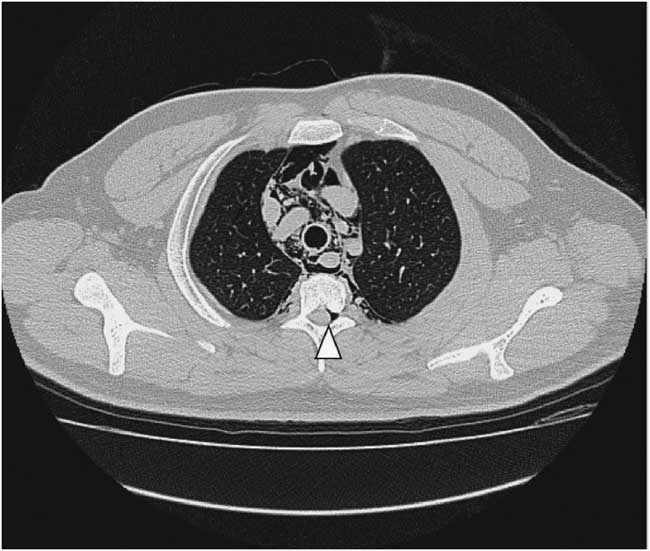

A 22-year-old male presented to the emergency department due to progressive odynophagia and dysphagia. He underwent a left third mandibular molar extraction at the dental clinic a week prior. At the emergency department, vital signs were normal except tachycardia (114/min) and tachypnea (22/min). A physical examination revealed bilateral neck tenderness with crepitus on palpation, no stridor or acute airway compromise signs. Laboratory data showed leukocytosis (white blood cell count, 19000/cumm; segmented, 91%) and elevated C-reactive protein (1.07 mg/dL). Radiographs showed the presence of prevertebral emphysema on the C-spine lateral view (Figure 1) and subcutaneous emphysema with pneumomediastinum on the chest posteroanterior view (Figure 2). A non-contrast computed tomography (CT) scan confirmed the radiographic findings; additionally, there was gas collection over the pericarotid, pericardial (Figure 3) and extradural spaces (Figure 4). Because there was no CT evidence of infectious signs and clinical features were stable, conservative treatment with intravenous amoxicillin/clavulanic acid was given for a week. Clinical symptoms improved, and a follow-up CT showed no residual gas.

Figure 2 Posteroanterior chest radiograph shows subcutaneous emphysema (arrow heads) and pneumomediastinum (arrows).